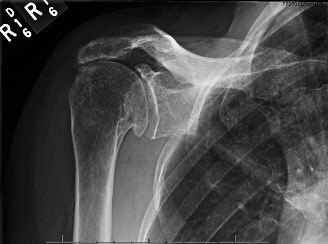

CASE 11 A 33-year-old male presents to the ED after a fall during a soccer game. He reports significant right shoulder pain and limited ROM. An x-ray taken in the ED is shown below (Fig. 2–29).

Figure 2–29

The correct answer is (A). The ED image shown in Figure 2–29 includes only an AP view of the right shoulder. In the setting of an acute injury and pain, technicians may be hesitant to obtain additional views. A single view, however, is insufficient to diagnose either a fracture, as orthogonal views are required, or a shoulder dislocation which is best seen on an axillary view (see Fig. 2–30). Answers B and C are inappropriate as a diagnosis has not been established yet and a dislocation or fracture must be conclusively ruled out. Answers D and E may be options that are exercised in the clinic but do not represent the next step in the management of this patient.

--- _Figure 2–30_A: Axillary view. B: Axillary view with annotations. Traumatic anterior instability is a common shoulder problem with an estimated incidence of 1.7%. This term encompasses both frank dislocations that require a manual reduction as well as incomplete subluxations that spontaneously reduce. It is particularly common in the young and athletic population, and it is significantly more common than other forms of instability including posterior or multidirectional instability. Understanding the natural history of anterior instability is important, as it serves as a guide to treatment. Young patients have a very high risk of recurrence; patients <20 years old have a 90% recurrence risk, between 20 and 40 years old have a 60% recurrence risk, and >40 years old have a 10% risk. Recurrent events are a predictor for arthritis and necessitate aggressive treatment, particularly in the young patient.